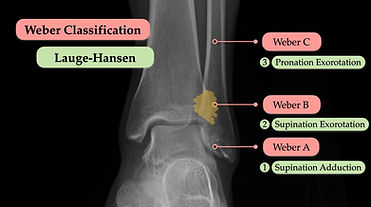

We believe that every clinician working in acute care should feel confident interpreting radiographic images—because timely, accurate image interpretation can directly impact patient outcomes. Yet too many providers leave training feeling unprepared for this critical skill.

As emergency medicine physicians, we created RapidRads to bridge that gap—empowering non-radiologist providers with the knowledge and confidence they need to succeed in the emergency department and beyond.